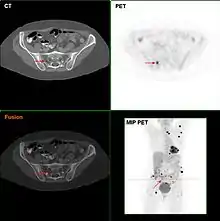

Metastatic melanomas can be detected by X-rays, CT scans, MRIs, PET and PET/CTs, ultrasound, LDH testing and photoacoustic detection.[85] However, there is lack of evidence in the accuracy of staging of people with melanoma with various imaging methods.[86]

It is common for patients diagnosed with melanoma to have chest X-rays and an LDH test, and in some cases CT, MRI, PET, and/or PET/CT scans. Although controversial, sentinel lymph node biopsies and examination of the lymph nodes are also performed in patients to assess spread to the lymph nodes. A diagnosis of melanoma is supported by the presence of the S-100 protein marker.